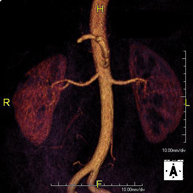

Prova diagnòstica no invasiva que consisteix en l'obtenció d'imatges d'alta definició anatòmica de tot el cos mitjançant l'ús d'un camp electromagnètic i ones de ràdio (amb un emissor i un receptor). No utilitza radiació ionitzant. És una prova molt important en la recerca de metàstasi en pacients amb neoplàsia coneguda. No requereix preparació prèvia. No és necessari l'ús de contrast paramagnètic (Gadolini). - Angio RM d'Aorta-ilíaca

Prova diagnòstica no invasiva que consisteix en l'estudi de l'artèria aorta abdominal i de les artèries ilíaques, amb l'obtenció d'imatges d'alta definició anatòmica mitjançant l'ús d'un camp electromagnètic i ones de ràdio (amb un emissor i un receptor). És indispensable l'ús de contrast paramagnètic (Gadolini). No utilitza radiació ionitzant. La qualitat de les imatges permet realitzar reconstruccions en 2D i 3D. Aquesta prova està especialment indicada com a estudi prequirúrgic (mapa vascular) abans d'intervencions percutànies o quirúrgiques d'aorta abdominal i artèries ilíaques, per a l'estudi complementari en pacients amb isquèmia de membres inferiors, etc. - Angio RM Arterial d'extremitats inferiors

Prova diagnòstica no invasiva que consisteix en l'estudi de l'artèria aorta abdominal per obtenir imatges d'alta definició anatòmica mitjançant l'ús d'un camp electromagnètic i ones de ràdio (amb un emissor i un receptor). És indispensable l'ús de contrast intravenós paramagnètic (Gadolini). No obstant, no utilitza radiació ionitzant. La qualitat de les imatges permet realitzar reconstruccions en 2D i 3D. Està indicat en aquells pacients amb malaltia vascular (Aterosclerosi), per a l'estudi d'aneurismes, en estudis prequirúrgics de lesions adjacents a l'aorta abdominal com "mapa" vascular, etc. - Angio-RM Aorta ilíaca

Prova diagnòstica no invasiva que consisteix en l'estudi de l'artèria aorta abdominal per obtenir imatges d'alta definició anatòmica mitjançant l'ús d'un camp electromagnètic i ones de ràdio (amb un emissor i un receptor). És indispensable l'ús de contrast intravenós paramagnètic (Gadolini). No obstant, no utilitza radiació ionitzant. La qualitat de les imatges permet realitzar reconstruccions en 2D i 3D. Aquesta prova està especialment indicada com estudi prequirúrgic (mapa vascular) abans d'intervencions percutànies o quirúrgiques d'aorta abdominal, per a l'estudi complementari en pacients amb isquèmia de membres inferiors, etc. - Angio-RM d'Artèries renals